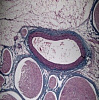

Сверхнадежные HD LCD-камеры, которые сочетают в себе камеру full HD и ЖК-экран retina HD. Благодаря встроенному программному обеспечению DLC-600AF камерами можно управлять с помощью мыши для фотосъемки, видеосъемки и проведения измерений. Оснащенный сенсором Sony COMS и 11,6-дюймовым ЖК-экраном retina HD разработан специально для различных применений в микроскопии. DLC-600 AF имеет функцию автофокусировки и фокусировки в один клик.

Подходят для использования в медицинской диагностике, промышленном производстве и инспекции, лабораторных исследованиях и смежных областях микроскопии для получения изображений, видеосъемки и анализа, а также в следующих областях:

• изображение живых клеток;

• хирургическая микроскопическая визуализация;

• патология;

• цитология;